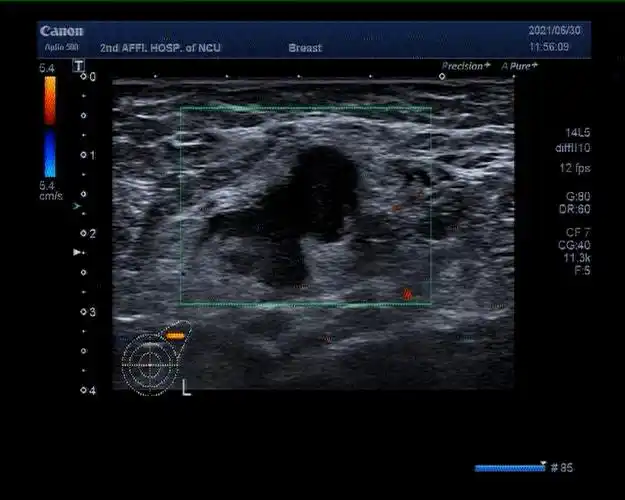

搜狐医药北京协和最新研究指南b超是最适合中国人的乳腺癌筛查手段

①常规筛查—血清肿瘤标志物②乳腺癌筛查—乳腺彩超/乳腺钼靶③宫颈

是乳腺曾经活检出乳腺癌或高风险癌前病变的患者,再次b超发现bi-rads

协和牵头制定中国指南发表b超是最适合国人的乳腺癌筛查手段